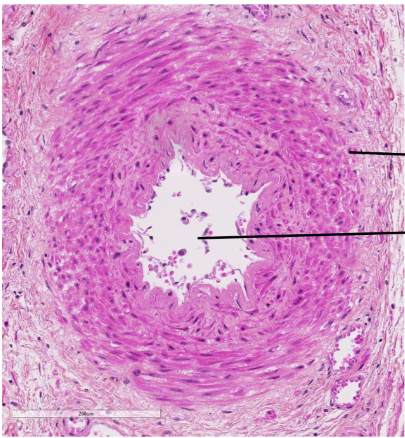

coupe transversale, longitudinale ou oblique et coloration

Transversale HES